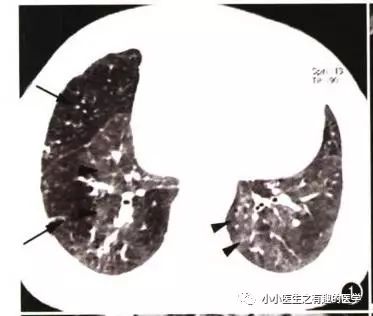

其实,我大中华也有医生用CT平扫发现可疑肺栓塞。

下面是上海交通大学的论文

↓↓↓

基本上看得到。

2004年,李铁一教授就说了:对于不能使用对比剂或因非典型心肺症状而仅作平扫的病例,肺动脉CT平扫的异常密度改变能提示急性肺动脉栓塞的存在。

高分辨CT平扫管腔内高密度征象诊断肺栓塞的敏感性36.0%, 特异性99.0%,阳性预测值90.0%,阴性预测值85.6% 。

高分辨CT平扫管腔内高密度征象诊断中心肺栓塞敏感性66.7%, 特异性99.1%。